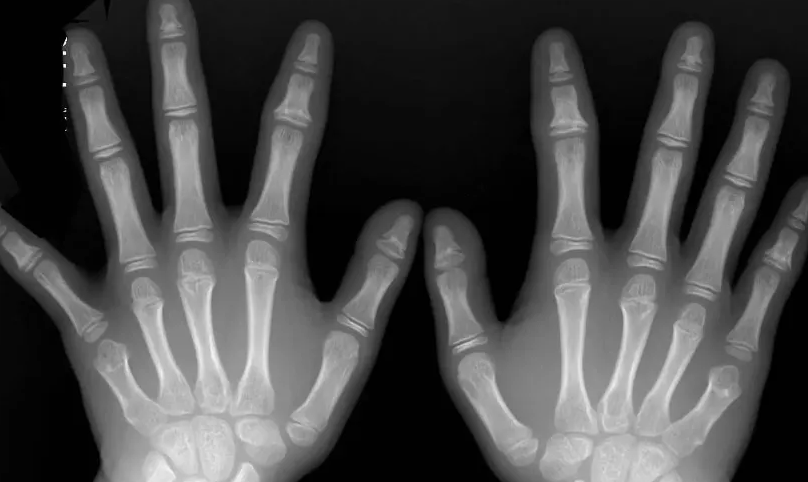

家长们忧虑小朋友身高的时候,一般都会带着孩子去医院做骨龄检测。由骨骺开始,小朋友的骨骼慢慢生长,生长到后期,身高的增长会趋于停止,这是因为骨骺线慢慢闭合了。

骨骺与干骺线之间,有一个软骨,这就是骨骺线。它是骨两端的软骨在生长发育的过程中呈现出来的骨化点,从X光片上看,它是一条宽宽的透光带。不同于其他不会骨化的软骨,像耳软骨、鼻软骨这些,骨骺线是跟着人体的生长一起逐渐骨化的。换句话说,骨骺线通过逐步的骨化,来延长长在四肢软骨上的时间,帮助身高去长高。

在年龄上升的过程中,骨骺线慢慢的变短了,直到它和干骺端的软骨彻底骨化,从一条线变成一条缝,这时候就代表着骨骼不再生长了,骨骺线彻底闭合了。通过骨骺线软骨细胞不断地进行增殖和骨化,小朋友的身高得以长高。时间推移过程中,性激素也在分泌,在青春期发育过了些时间后,原本存在固有程序性变化的骨骺线开始有了趋于衰老的变化,包括功能性和组织性两个方面,与此同时,软骨细胞也失去了繁殖和骨化的能力,因此软骨骨化的空间和原料也消耗完了,这个过程便是骨骼线闭合,经过这个过程,身高也就不再增长了。骨骺线闭合的时间并不是固定的,不同的小朋友存在着个体差异性。对于女孩子来说,有些12岁就闭合,有些14-16岁左右,相对早一些;而男孩则晚一点,有些16-18岁,还有的人更晚点。

如果确认骨骺线闭合,一切都晚了,因为此时再先进的医疗手段也毫无办法。因此,家长们应该经常留意小朋友的生长发育情况,不放心的时候,带到医院进行检查,通过骨龄片可以看到小朋友骨骺线的真实状况,一旦发现有了闭合的可能,就要听从医生的医嘱来进行治疗。